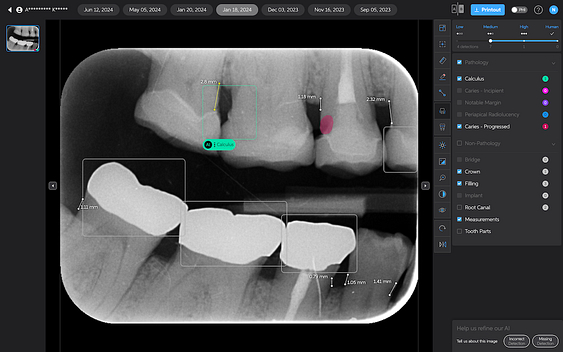

Calculus Detection

Green squares highlight areas of radiographic calculus. This tool is useful for hygienists and dentists in treatment planning and patient education.

Quite self-explanatory and the system didn't seem to miss often, if ever.

Notable Margins

Purple squares indicate areas of notable margins, such as potential overhangs or open margins on existing restorations.

This is particularly useful as well. I find that patients hate hearing that there is secondary decay at the edge of a crown, for example. And it is always a touchy subject if it is a recent crown done elsewhere. With AI, you are effectively removing yourself and any perceived sales bias from the diagnosis. This is what the AI shows.

Great feature.

Periapical Radiolucencies

These are self-explanatory. They are outlined in blue on periapical radiographs. While this could help draw attention to potential issues, interpreting these findings would still rely heavily on the dentist's expertise.